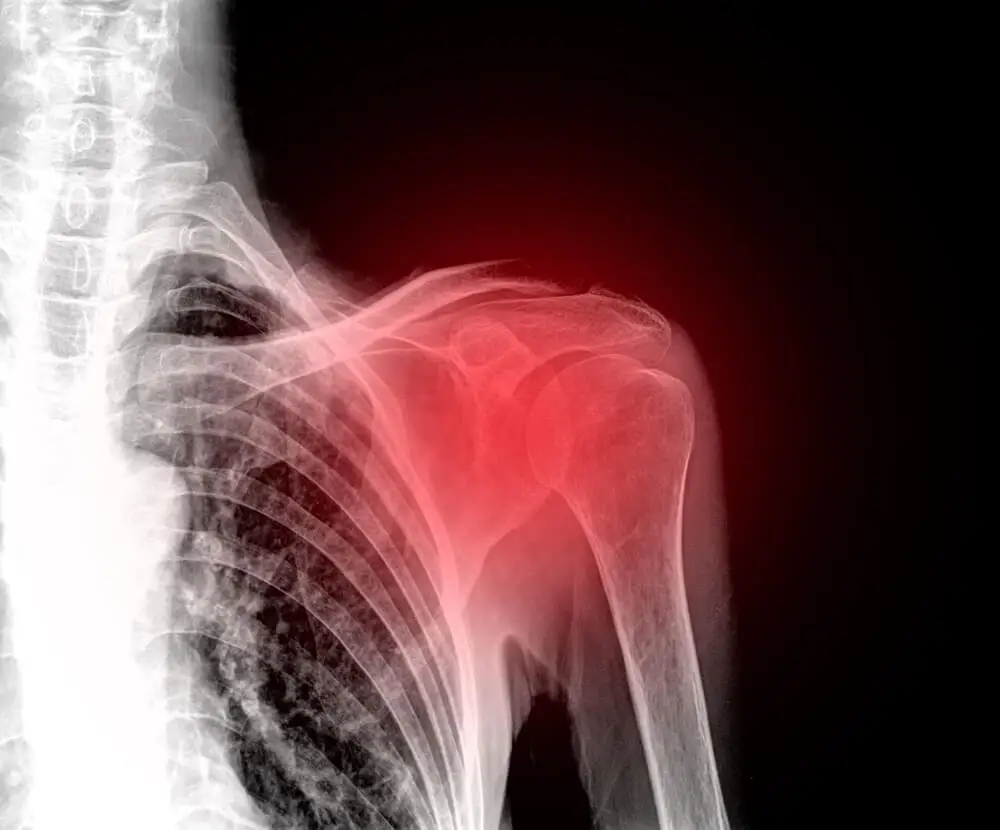

Un gesto improprio, una postura scorretta o lo stress possono originare fastidio e dolore alla spalla. Si tratta di un problema comune e tipico di chi lavora molto alla scrivania o al computer.

La spalla è l’insieme di articolazioni che unisce il braccio al tronco. È formata da tre ossa (omero, scapola e clavicola) e da vari muscoli, legamenti e tendini che le conferiscono stabilità e movimento.

A causa dell’ampia gamma di attività quotidiane a cui partecipa, è suscettibile di subire lesioni lievi o gravi.

Le tipiche attività che possono acuire il dolore alla spalla sono i lavori domestici, esercizi fisici intensi che richiedono il movimento delle braccia o aver praticato sport senza essersi riscaldati, spostamento o sollevamento di oggetti pesanti, ecc.